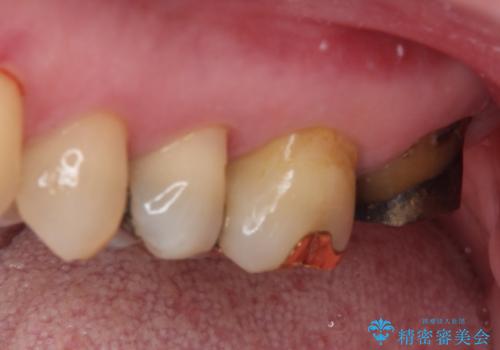

- 奥歯のクラウンが外れてしまったとのことで来院された患者様です。

土台の歯は、咬み合う下顎の歯と距離が近く、外れてしまったクラウンは、おそらく穴が空いてしまったのではないかと思われました。

距離が近いこと以外、特に大きな問題は認められなかったため、ゴールドクラウン(PGAクラウン)にて補綴することとしました。

上の奥歯であることから、審美性よりも機能性を優先され、ゴールドクラウンを選択されました。